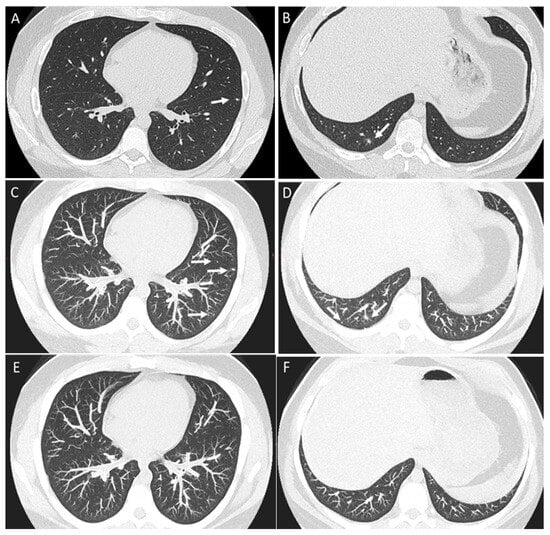

2.1. Parenchymal Metastasis

2.2. Vascular Metastasis

2.3. Endobronchial Metastasis

2.4. Lymphangitic Carcinomatosis